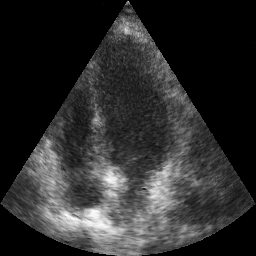

Transthoracic echo is one of the most common means of cardiac studies in the clinical routines. During the echo exam, the sonographer captures a set of standard cross sections (echo views) of the heart. Each 2D echo view cuts through the 3D cardiac geometry via a unique plane. Consequently, different views share some limited information. In this work, we investigate the feasibility of generating a 2D echo view using another view based on adversarial generative models. The objective optimized to train the view-conversion model is based on the ideas introduced by LSGAN, PatchGAN and Conditional GAN (cGAN). The size and length of the left ventricle in the generated target echo view is compared against that of the target ground-truth to assess the validity of the echo view conversion. Results show that there is a correlation of 0.50 between the LV areas and 0.49 between the LV lengths of the generated target frames and the real target frames.